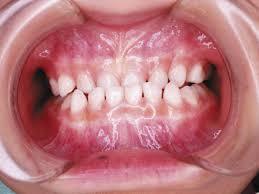

顎が小さいお子さまの場合、永久歯が正しく生えるスペースが足りず、歯がガタガタになってしまうことがあります。小児矯正で顎を広げることで、永久歯がきれいに並ぶための土台を築きます。

ガタガタの歯並び(叢生): 歯がデコボコに生えている

第1期治療は、主に成長期の顎の骨を正しい方向に誘導し、永久歯がきれいに生えそろうためのスペースを確保することが目的です。